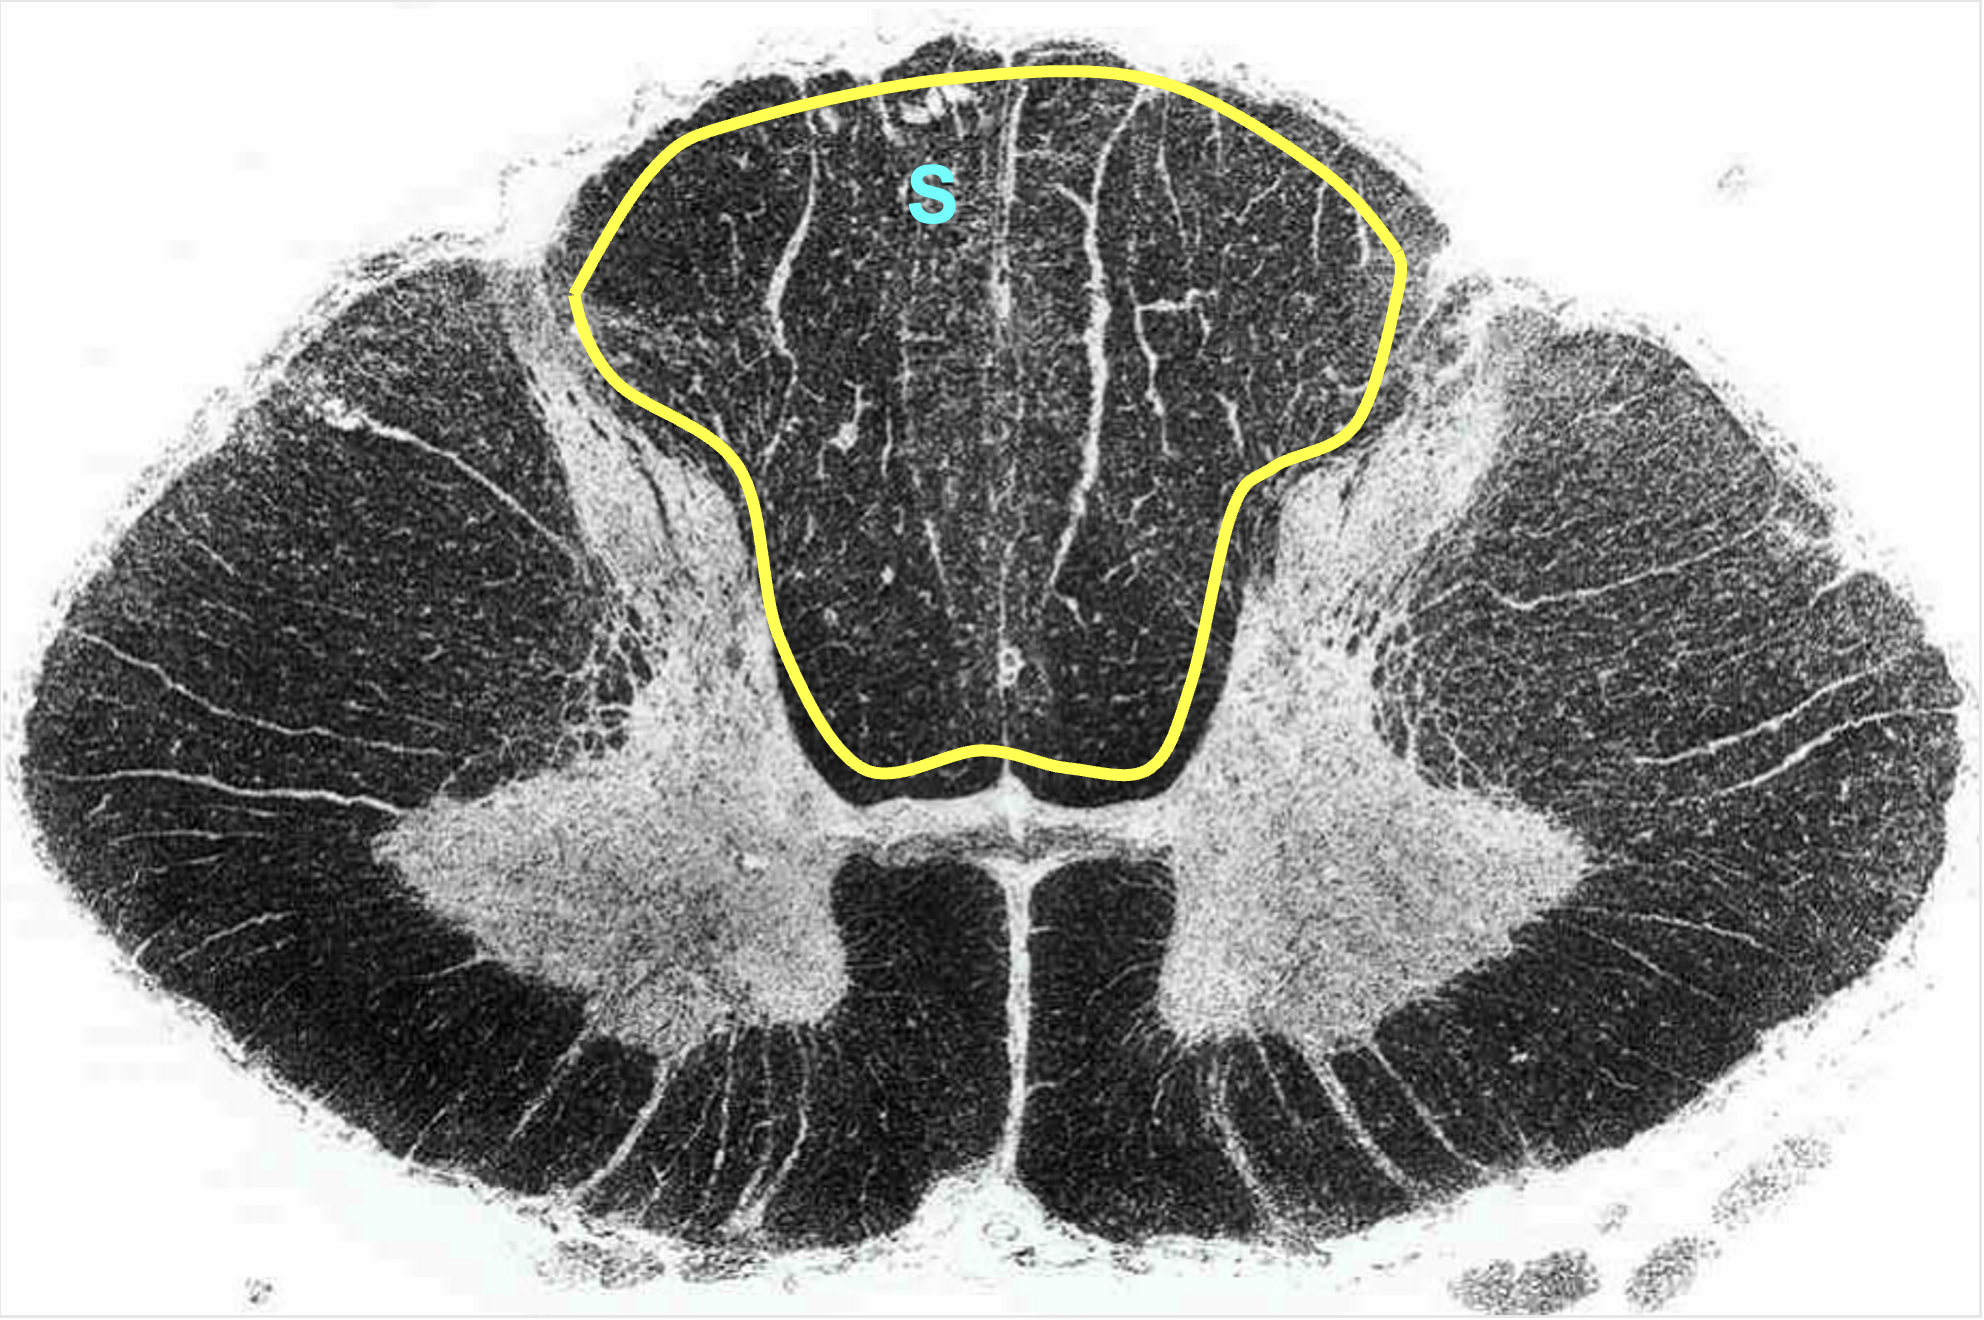

butterfly

center of the spinal cord; contains neurons and glia (grey matter)

grey matter

primarily made up of neurons (cell bodies)

white matter

primarily made up of myelinated axons

dorsal column/funiculus

white matter located in between dorsal horns; contain multiple tracts

sensory information (ascending)